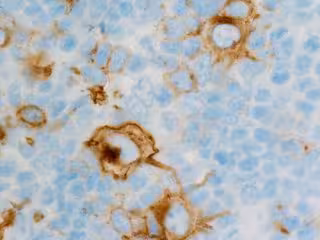

Linfoma de Hodking

FLIKR/CNICHOLSONPATH - Archivo

La Organización Mundial de la Salud (OMS) establece la existencia de más de 40 tipos de linfoma, en función del tipo de células inmunes afectadas y los biomarcadores implicados. De manera general, existen dos grandes grupos: los linfomas de Hodgkin (LH), que suponen el 10% de todos los casos y se curan en la mayoría de los pacientes, y los linfomas no Hodgkin (LNH), que suponen el 90% restante y constituyen un gran reto desde el punto de vista de su abordaje.